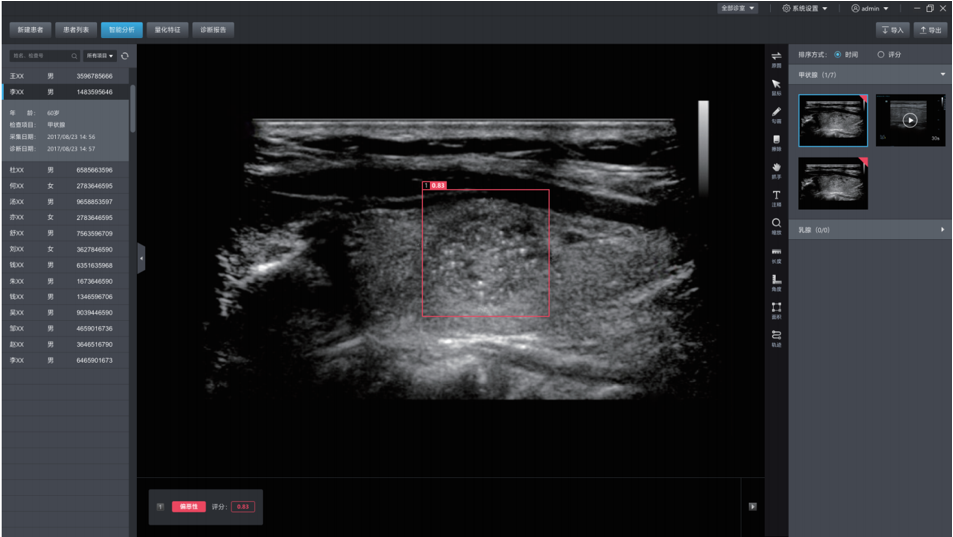

DEMETICS 超聲診斷機(jī)器人

德尚韻興醫(yī)療科技采用自主研發(fā)的深度學(xué)習(xí)框架DE-Light, 在專(zhuān)家標(biāo)注的大量樣本基礎(chǔ)上,研發(fā)的超聲輔助診斷系統(tǒng),可自動(dòng)探測(cè)超聲圖像中的病灶,并自動(dòng)判斷良惡性。甲狀腺結(jié)節(jié)良惡性的準(zhǔn)確率達(dá)到85%,達(dá)到三甲醫(yī)院主治醫(yī)生的水平。